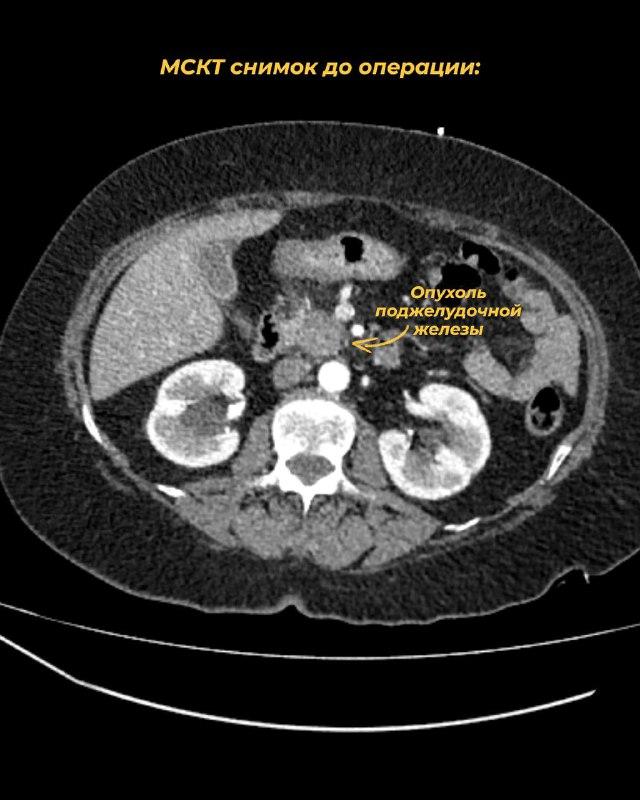

В отделе торакоабдоминальной онкохирургии ИвООД успешно выполнено очередное вмешательство высокого уровня сложности - панкреатодуоденальная резекция. Каждая такая операция - значимая победа над одной из самых агрессивных болезней, раком поджелудочной железы.

Пациентка 69 лет заметила пожелтение кожных покровов и обратилась к врачу по месту жительства. Далее она была направлена в онкодиспансер с подозрением на опухоль головки поджелудочной железы. На первом этапе врачами отделения рентгенхирургических методов диагностики и лечения ИвООД Арсентьевым Д.В. и Сусловым Д.А. была устранена угроза жизни - желтуха. Под местным обезболиванием доктора успешно выполнили дренирование внутрипеченочных желчных протоков. Вскоре после этого на мультидисциплинарном консилиуме было проведено обсуждение тактики дальнейшего лечения пациентки.

Параллельно с лечением в Ивановском онкодиспансере пациентка самостоятельно обратилась за вторым мнением в одну из клиник столицы, где опухоль была признана неоперабельной и были даны рекомендации проводить химиотерапию. Но, основываясь на собственном опыте и мировой статистике, ивановские хирурги придерживались другого мнения. Повторно выполнив КТ и тщательно проанализировав его с построением 3D-реконструкций сосудов, врачи не нашли препятствий для радикальной хирургии и предложили пациентке операцию. Дело в том, что именно хирургическое лечение является основным при резектабельном раке поджелудочной железы, а лекарственный метод применяется в большинстве случаев после радикальной операции как мера профилактики рецидива.